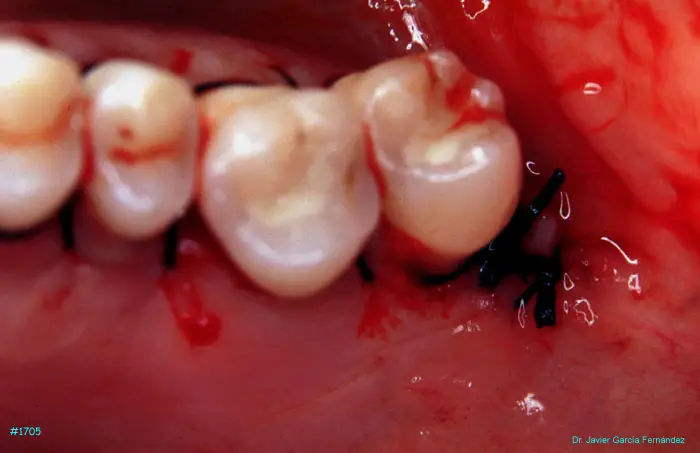

Atlas of Surgical Techniques in Periodontics. Chapter IV. Atlas de Técnicas Quirúrgica en Periodoncia

image 216